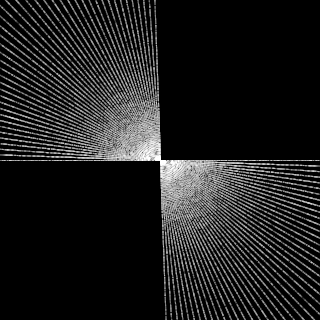

This article presents a novel undersampled magnetic resonance imaging (MRI) technique that leverages the concept of Neural Radiance Field (NeRF). With radial undersampling, the corresponding imaging problem can be reformulated into an image modeling task from sparse-view rendered data; therefore, a high dimensional MR image is obtainable from undersampled $k$-space data by taking advantage of implicit neural representation. A multi-layer perceptron, which is designed to output an image intensity from a spatial coordinate, learns the MR physics-driven rendering relation between given measurement data and desired image. Effective undersampling strategies for high-quality neural representation are investigated. The proposed method serves two benefits: (i) The learning is based fully on single undersampled $k$-space data, not a bunch of measured data and target image sets. It can be used potentially for diagnostic MR imaging, such as fetal MRI, where data acquisition is relatively rare or limited against diversity of clinical images while undersampled reconstruction is highly demanded. (ii) A reconstructed MR image is a scan-specific representation highly adaptive to the given $k$-space measurement. Numerous experiments validate the feasibility and capability of the proposed approach.